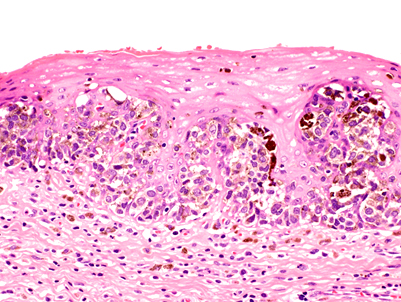

Microscopic (histologic) description

- Mostly epithelioid tumor cells with at least focal melanin pigment (Mod Pathol 2019;32:957)

- Associated melanoma in situ component (junctional melanocytic activity / junctional melanocytic component / tumor nests at the epithelium - lamina propria junction / horizontal tumor spread in the basal layer of the epithelium) and melanocytosis / melanosis (Mod Pathol 2019;32:957, Ann Thorac Surg 2013;96:1002)

Microscopic (histologic) images

A. Junctional melanocytic activity (shown in the picture) suggests a primary malignant melanoma of the esophagus